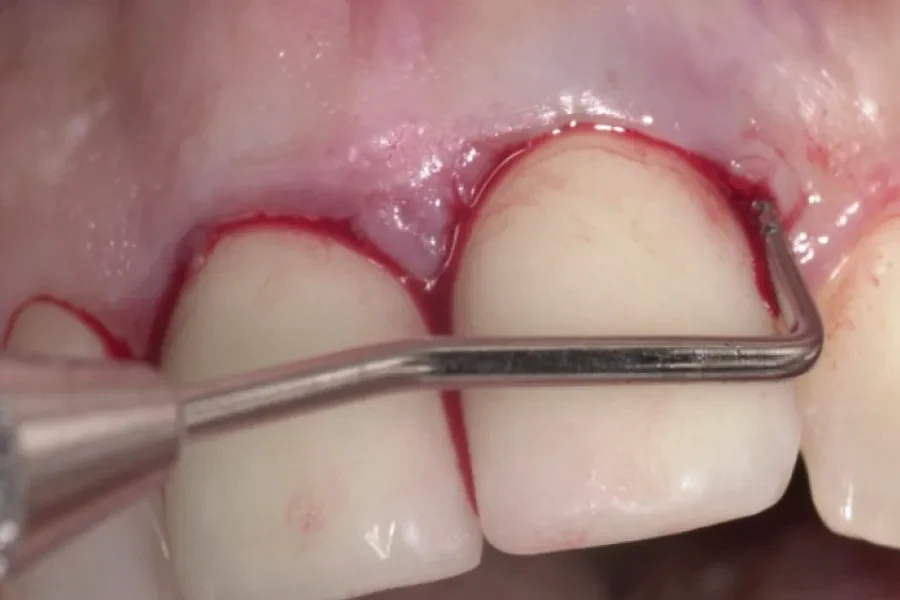

2. Зонды: Используются для измерения глубины карманов и оценки тяжести парадонтальных заболеваний.

3. Улучшение результатов лечения: Использование ручных инструментов в диагностике и лечении парадонтальных заболеваний показало улучшение результатов лечения, включая уменьшение глубины карманов и улучшение здоровья десен.